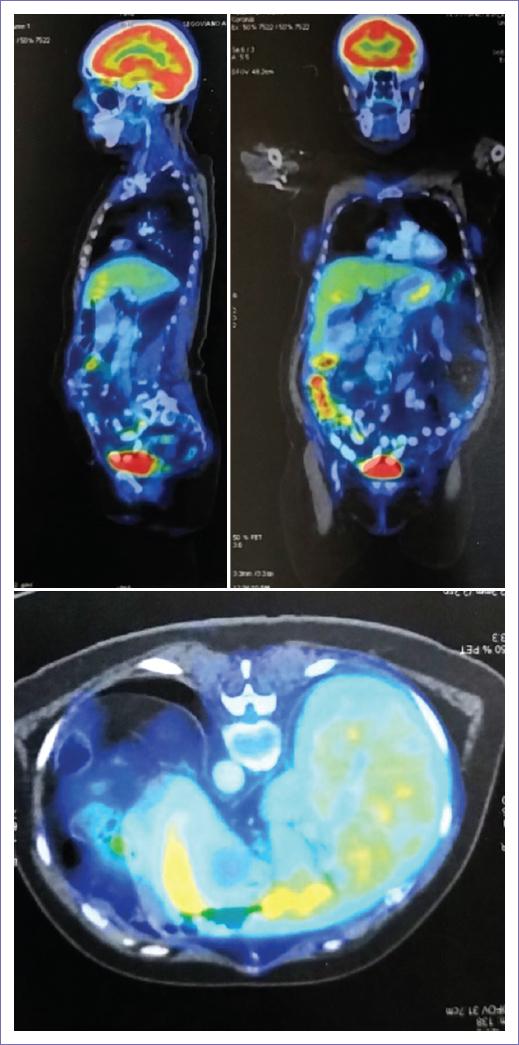

18FDG PET/CT: 26.04.22: Study without macroscopic morphometabolic evidence of tumoral activity. Post-surgical changes due to subtotal pancreatectomy, splenectomy, and hysterectomy. Hepatic steatosis. Signs of spinal degenerative osteoarticular pathology (Fig. 4).

Figure 4 April 26, 2022. F-FDG PET/Whole body CT: no macroscopic anatomical-metabolic evidence of tumor activity. Post-surgical changes due to subtotal pancreatectomy, splenectomy, and hysterectomy.